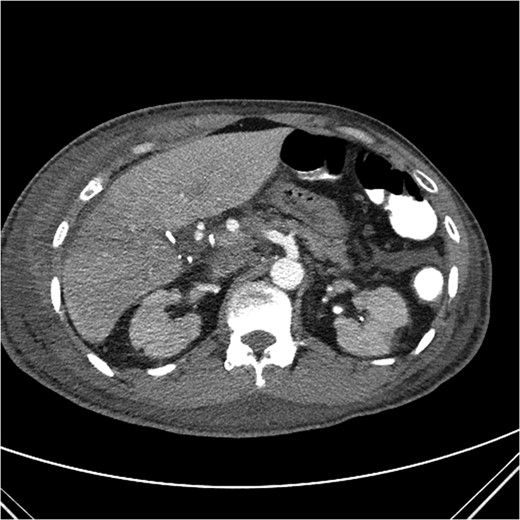

A computed tomography (CT) angiogram of the abdomen was significant for multifocal pneumonia and free peritoneal fluid. Chest CT was negative for pulmonary embolism (Figs 1, 2). Repeat ERCP confirmed a wide-open distal common bile duct at the level of multiple surgical clips with inability to pass a wire distally (Fig. 3). Interventional radiology was consulted to obtain a percutaneous transhepatic cholangiography (PTC) prior to definitive surgical repair.

Axial CT image with clip artifact surrounding the location of the bile duct.